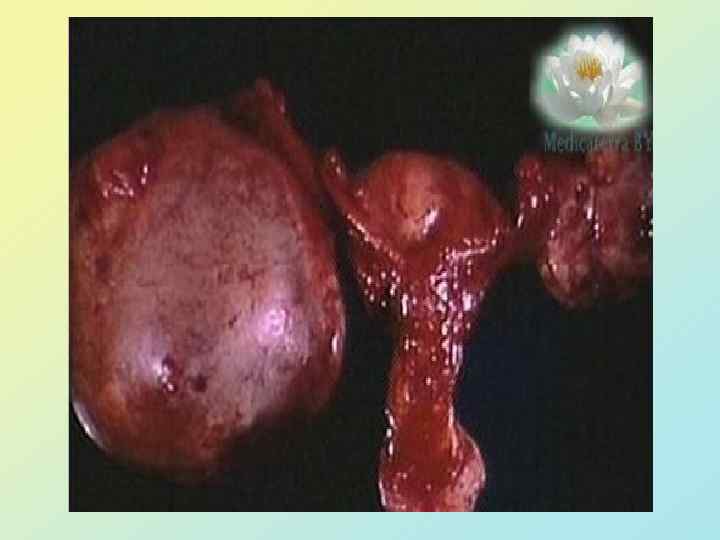

Жайылған АБО (III –IV сатысы)

Паллиативтік операциялар Кіші жамбас қуысының ісіктік инфильтрациясы, Ішектің көптеген зақымдалуы – эксплоративтік лапаротомия локальді ісік, ішектің резекциясы жасалған